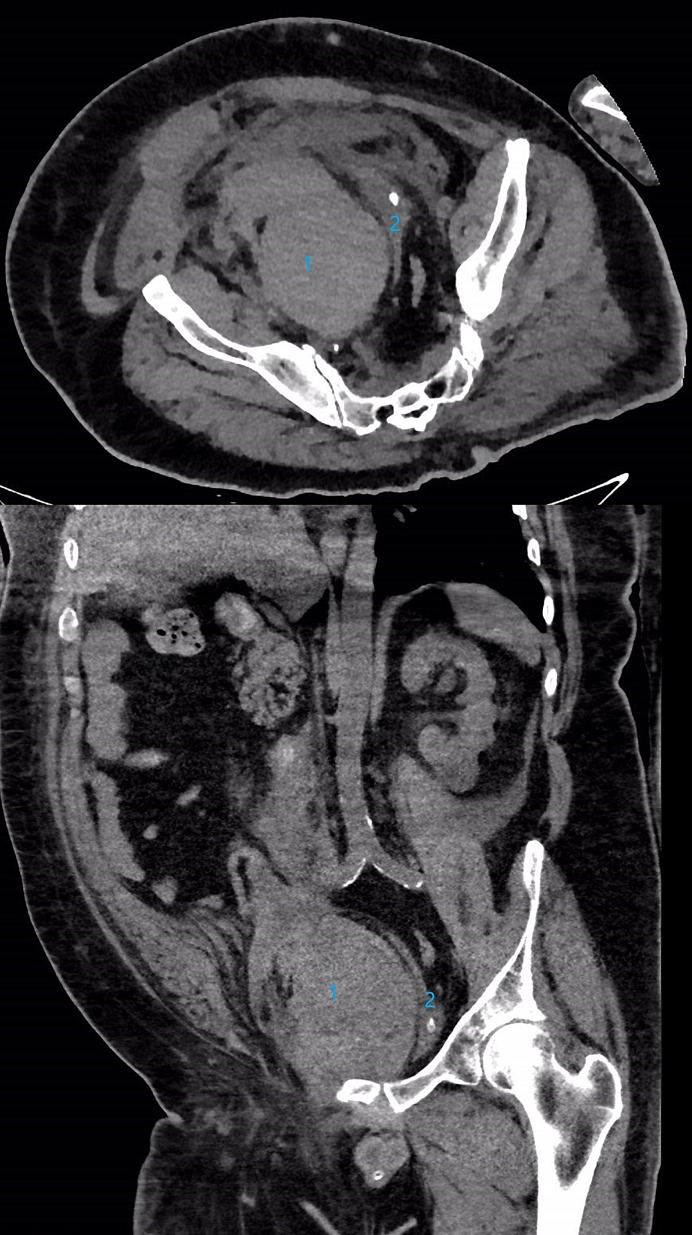

Case report: A morbidly obese man in his late 50s was admitted with complications of COVID-19, including acute respiratory syndrome, bilateral peroneal deep vein thromboses, and acute kidney injury. He was treated with anticoagulants (subcutaneous enoxaparin and apixaban), dexamethasone, and remdesivir. He developed severe abdominal pain, and a large (14 × 17 cm) right rectus sheath and an extraperitoneal pelvic hematoma were identified by computed tomography. The hematoma extended across the midline into the left pelvis and the retroperitoneum with associated mild right hydronephrosis. A handheld percussive massage device (Theragun®) was applied repeatedly at the site of enoxaparin injection into the abdominal wall in attempts to alleviate the pain. On day 12, bilateral nephrostomy tubes were inserted. A nephrostogram revealed mild hydroureteronephrosis to the ureterovesicular junction bilaterally and extrinsic compression of the bladder. On day 17, the patient suffered a cardiac arrest and died.